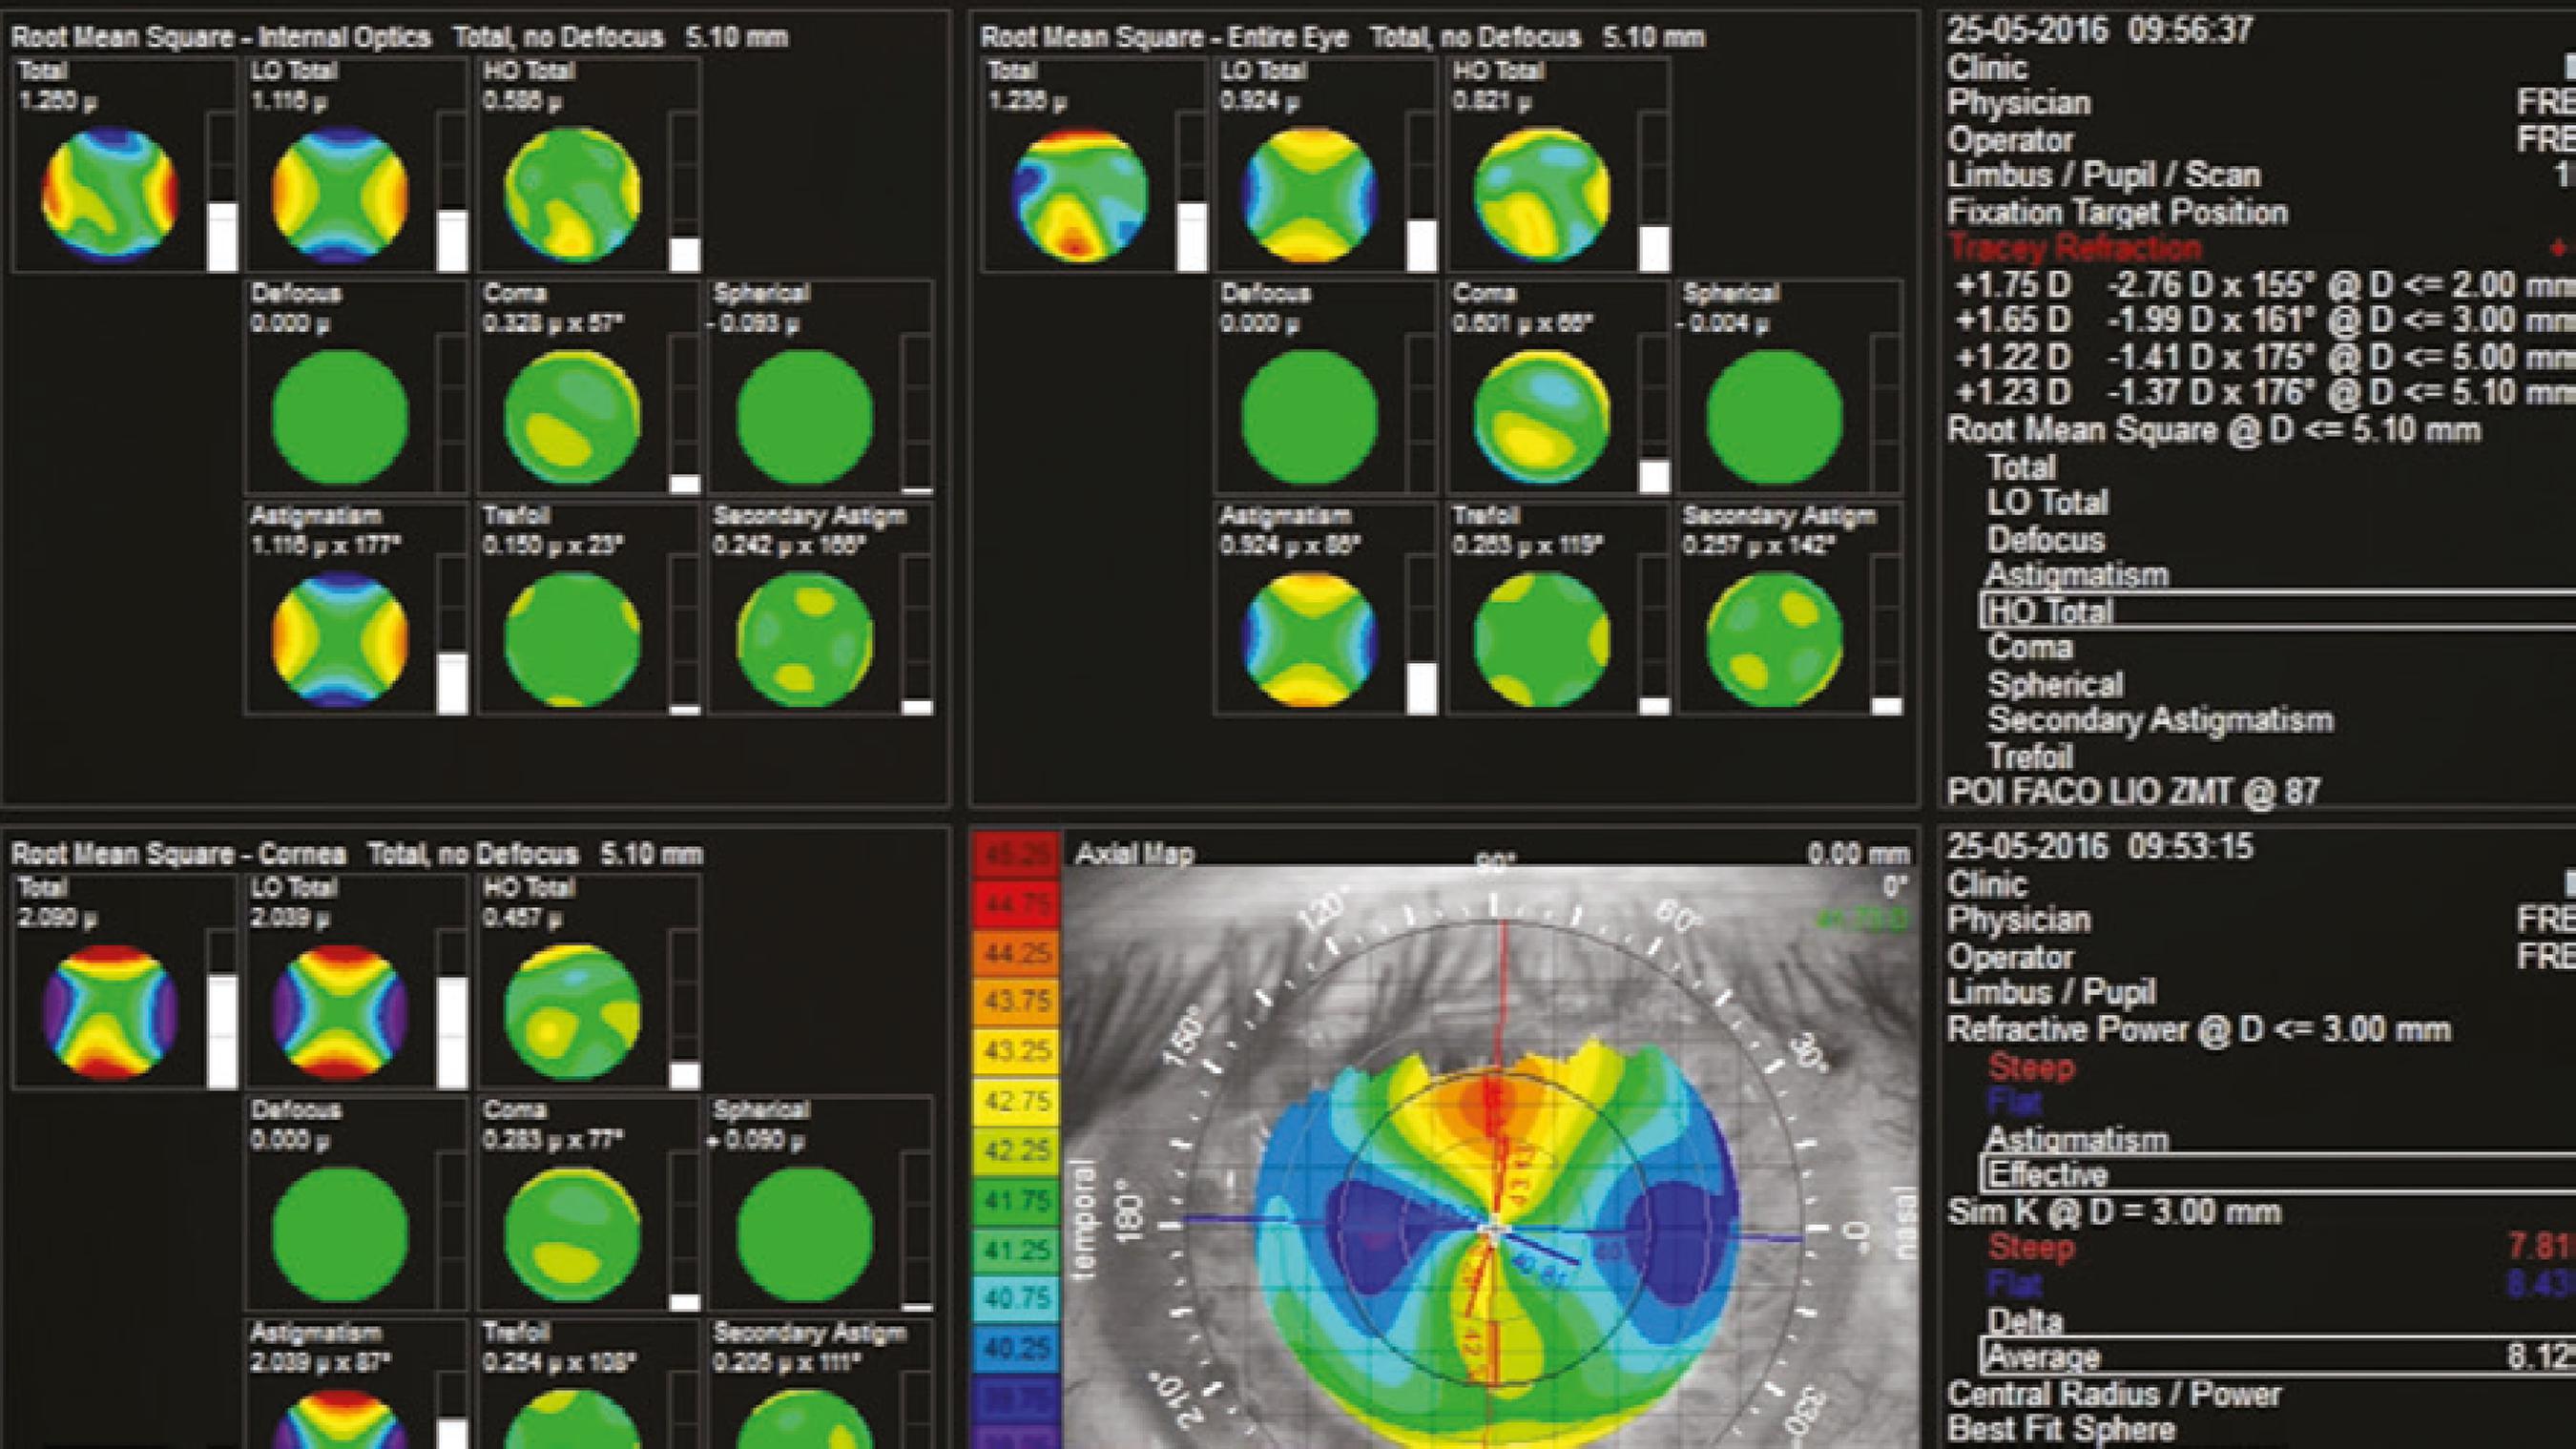

The simulated keratometry readings were 41.02 × 43.56 @ 93º in the OD and 41.61 × 42.5 @ 104º in the OS (iTrace; Tracey Techno logies LLC, Houston, TX, USA). Axial length measured 27.32 mm in the OD and 27.51 mm in the OS; ACD measured 4.12 mm in the OD and 4.18 mm in the OS; and the white-to-white (W-W) diameter was 13.7 mm in the OD and 14 mm in the OS as measured using an IOLMaster® 500 (Carl Zeiss AG, Oberkochen, Germany). The findings of optical coherence tomography of the maculae were normal in both eyes.

After thorough discussion of the oversized capsular bag and possible IOL decentration with the patient, we decided to implant bilateral multifocal IOLs. For the first eye (OS), after performing an uneventful phacoemulsification, we implanted a non-toric +12.0 Tecnis ZMA00 (Abbott Medical Optics Inc., Santa Ana, CA, USA) into the capsular bag with no complications regarding IOL centration. The patient achieved excellent postoperative visual acuity on Day 1 with an uncorrected visual acuity (UCVA) of 20/20 and J1. Regarding the other eye, because of its corneal astigmatism, a Tecnis ZMT300 (Abbott Medical Optics Inc.) toric 13.0 D multifocal IOL was placed at 87º.

On Day 1, his UCVA was 20/30 and J2 p, and the IOL was on the correct axis (Figure 3). One week later, the patient was very pleased with his UCVA of 20/25 J2, with a manifest refraction of +0.25 -0.50 @ 10º achieving the same visual acuity because of some degree of amblyopia probably originating from the higher corneal astigmatism in this eye.